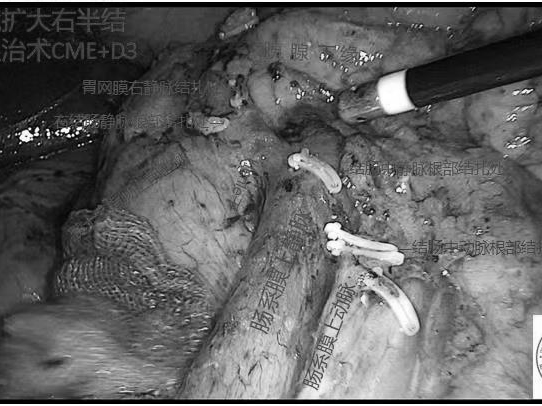

规范化肿瘤治疗

胃肠外科二病区(结直肠肛门外科)作为“中华结直肠癌MDT联盟成员单位”,一直致力于规范化的结直肠肿瘤治疗。二附院MDT核心小组成员包括胃肠外科二病区(结直肠肛门外科)、肝胆外科、肿瘤内科、肿瘤放射治疗科、影像科、病理科,胸心血管外科和护理部及其他科室成员根据情况参加,为患者确定治疗目标、制定治疗方案,进行个体化治疗。包括新辅助放化疗、转化治疗、靶向治疗、免疫治疗、手术治疗等。手术切除癌灶仍是肿瘤治疗最主要的治疗方式,科室开展标准的结直肠癌手术治疗包括:微创精细化的腹腔镜手术、结肠癌CME+D3根治术(全结肠系膜切除+第三站淋巴结清扫术)、直肠癌TME(全直肠系膜切除术)、TEM(经肛门内镜微创手术)、TaTME手术(经肛门全直肠系膜切除术)、NOSES手术(经自然腔道取出标本的腹壁无辅助切口手术)、低位及超低位直肠癌个体化保肛及保护自主神经功能(性功能、排尿功能)手术,根据患者病情及身体状况选择最有利于患者的治疗方案。

部分术中图片及术后肿瘤标本展示

↓↓↓